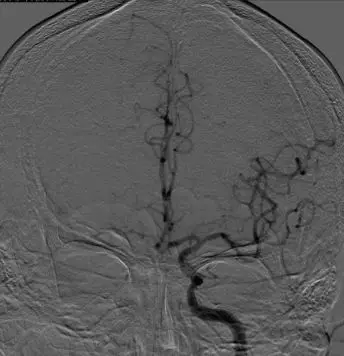

影像学表现与临床症状不匹配,发病超7小时。 DSA: 右侧颈内动脉C1段闭塞;右侧大脑中动脉M1段闭塞,颈外动脉经眼动脉向颅内代偿。

前交通动脉开放,同侧大脑前动脉通过软脑膜支代偿右侧大脑中动脉供血区域。

后循环通过软脑膜支及后交通动脉部分代偿右侧大脑中动脉供血区。